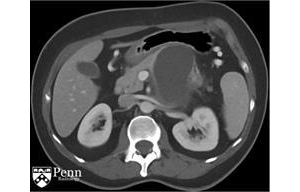

胰腺罕见病变:粘液性囊性肿瘤一例

基本病史:55岁女性,左腰痛。腹部增强CT如下图所示。影像学特征:来源于胰体/尾部的巨大的分叶状的囊性肿块,包绕脾动脉。其内可见一致密物在病变的内部下方与其分层。脾静脉内形成血栓,导致明显的胃肝和胃脾静脉 ...